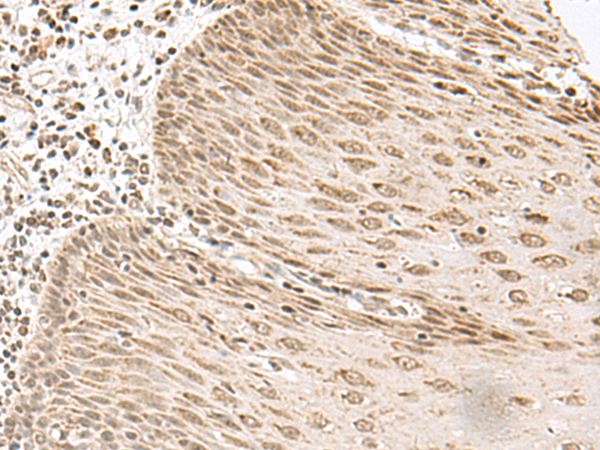

The image is immunohistochemistry of paraffin-embedded Human esophagus cancer tissue using P13439(LGALS4 Antibody) at dilution 1/35. (Original magnification: ×200) |